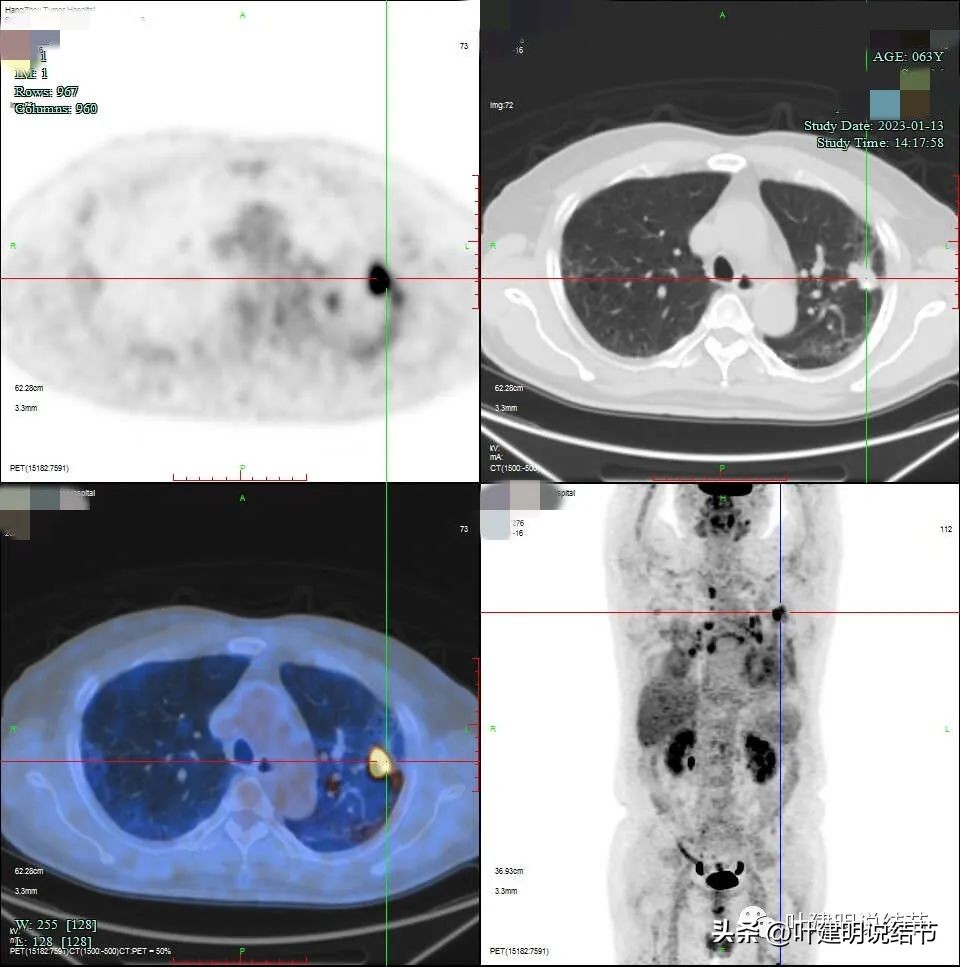

有钙化是不是考虑良性的呢?一般来说病灶伴钙化容易是良性,但这个病例恶性的影像太多太明显,所以再来看PET影像:

病灶处

右侧给隔淋巴结

左上病灶虽有钙化,但葡萄糖代谢增高,有诸多恶性影像表现的特征,仍需要考虑恶性可能性大,至少要取得病理以确定或排除肺癌。肺门与纵隔淋巴结的肿大与葡萄糖代谢高摄取,结合两肺炎性改变的表现,以及肿瘤的生物学行为,转移不容易解释,炎性的容易解释。